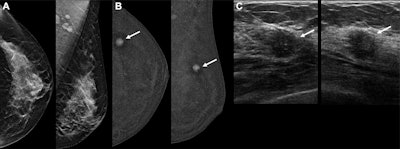

Images depict a 61-year-old woman with heterogeneously dense breasts and a family history of breast cancer in her mother, who was diagnosed at age 65. The participant’s estimated lifetime risk of breast cancer was 15% according to Tyrer-Cuzick, version 8.0. (A) Craniocaudal (left) and mediolateral oblique (right) mammograms show heterogeneously dense breast tissue, which may obscure detection of small masses; these appear normal even in retrospect. (B) Craniocaudal (left) and mediolateral oblique (right) recombined images from contrast-enhanced mammography (CEM) obtained following intravenous injection of 100 mL of iopamidol 370 show a high-conspicuity enhancing round mass in the upper outer left breast (arrows), assessed as BIRADS 4B by both readers. (C) Targeted transverse (left) and sagittal (right) ultrasound images show an indistinctly marginated, round, hypoechoic, 7-mm mass in the 1 o’clock position of the left breast, 3 cm from the nipple (arrows) that appeared to correspond to the CEM finding. Ultrasound-guided core biopsy and excision revealed a 1.1-cm, grade 1 invasive ductal carcinoma with ductal carcinoma in situ that was estrogen receptor positive and progesterone receptor and human epidermal growth factor 2 negative, with a Ki-67 proliferation index of 15%. Two sentinel nodes were negative.Images depict a 61-year-old woman with heterogeneously dense breasts and a family history of breast cancer in her mother, who was diagnosed at age 65. The participant’s estimated lifetime risk of breast cancer was 15% according to Tyrer-Cuzick, version 8.0. (A) Craniocaudal (left) and mediolateral oblique (right) mammograms show heterogeneously dense breast tissue, which may obscure detection of small masses; these appear normal even in retrospect. (B) Craniocaudal (left) and mediolateral oblique (right) recombined images from contrast-enhanced mammography (CEM) obtained following intravenous injection of 100 mL of iopamidol 370 show a high-conspicuity enhancing round mass in the upper outer left breast (arrows), assessed as BIRADS 4B by both readers. (C) Targeted transverse (left) and sagittal (right) ultrasound images show an indistinctly marginated, round, hypoechoic, 7-mm mass in the 1 o’clock position of the left breast, 3 cm from the nipple (arrows) that appeared to correspond to the CEM finding. Ultrasound-guided core biopsy and excision revealed a 1.1-cm, grade 1 invasive ductal carcinoma with ductal carcinoma in situ that was estrogen receptor positive and progesterone receptor and human epidermal growth factor 2 negative, with a Ki-67 proliferation index of 15%. Two sentinel nodes were negative.RSNA